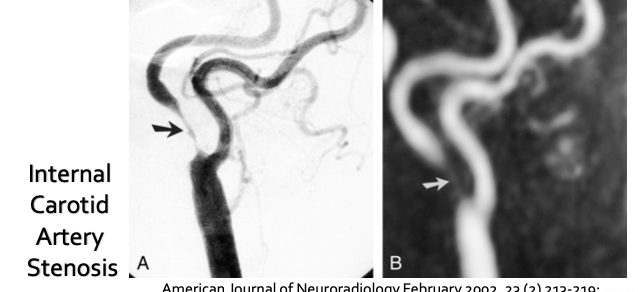

What is a bruit?

→ “whoosh" sound

sound of turbulence in blood flow when the normal laminar flow is disrupted by the narrowing (stenosis) of the artery

If a bruit is audible, what % of patients have been shown to have significant stenosis on angiography?

77%